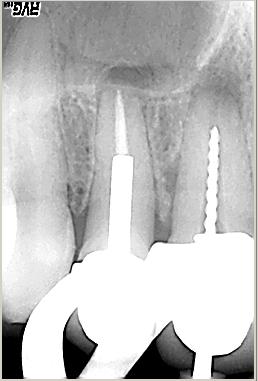

Masterpoinaufnahme

Masterpoinaufnahme. Mesial konnte keine „Patency“, das bewußte offenhalten des foramen apicale, hergestellt werden. Das distale Kanalsystem konnte gängig gemacht werden